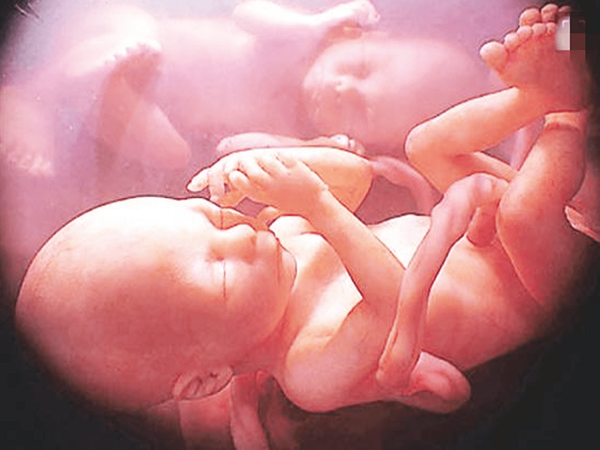

怀双胞胎真没想象中那么好,这个月份又累又难熬别不知道

众所周知,多胎妊娠的发生几率是非常低的,但是双胎妊娠是多胎妊娠中发生率较高的,因此孕妇在发现自己怀上双胞胎之后都会觉得非常高兴。但其实双胎妊娠给孕妇身体上带来的..